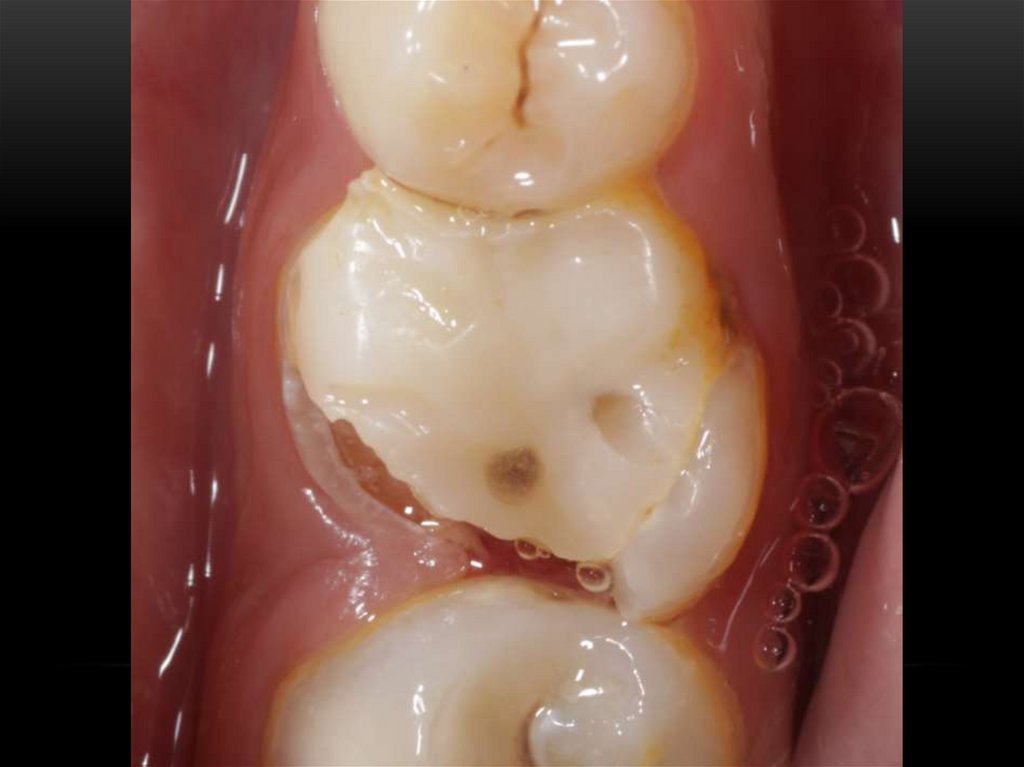

Механическая обработка корневых каналов. Этапы эндодонтического лечения

Принципы препарирования корневых каналов. Алгоритмы эндодонтического лечения

Эндодонтическое лечение зубов. Инструментальная обработка корневых каналов. Лекция 3-4

Лечение корневых каналов